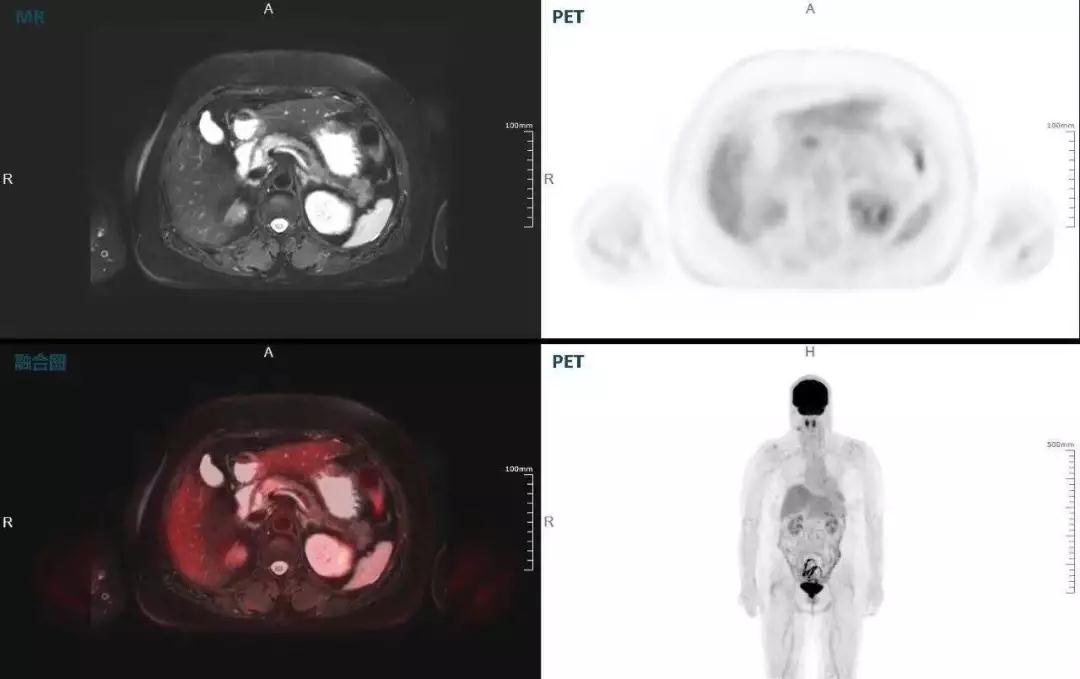

胰腺癌

中山醫(yī)院核醫(yī)學(xué)科在臨床實(shí)踐中發(fā)現(xiàn),基于聯(lián)影“時(shí)空一體”超清TOF PET/MR,不僅解剖信息和代謝信息能夠完美融合呈現(xiàn),同時(shí)精細(xì)展示局部病灶與周圍組織的復(fù)雜關(guān)系,并能全盤檢測病灶的全身轉(zhuǎn)移,為醫(yī)生臨床診斷提供更豐富信息。

(胰腺腫瘤,MR顯示胰腺體部信號異常,PET顯示稍高攝取,結(jié)構(gòu)改變和功能異常提示胰腺M(fèi)T可能大。)